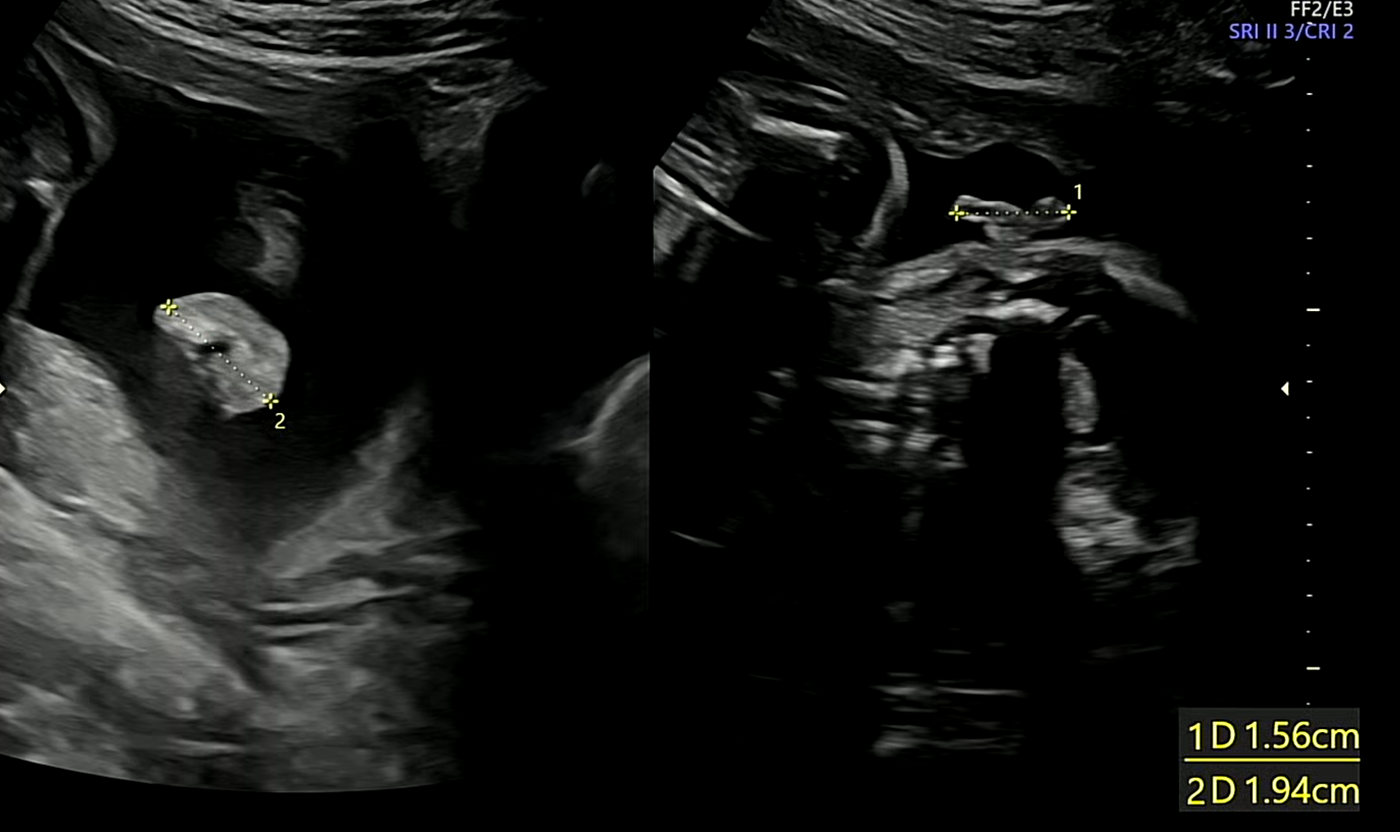

귀

귀도 문제없이 잘 형성되고 있음을 보았다. 우리 호띵이가 가장 먼저 세상을 만날 수단중 하나인 만큼 무럭무럭 잘 자라길 바란다.